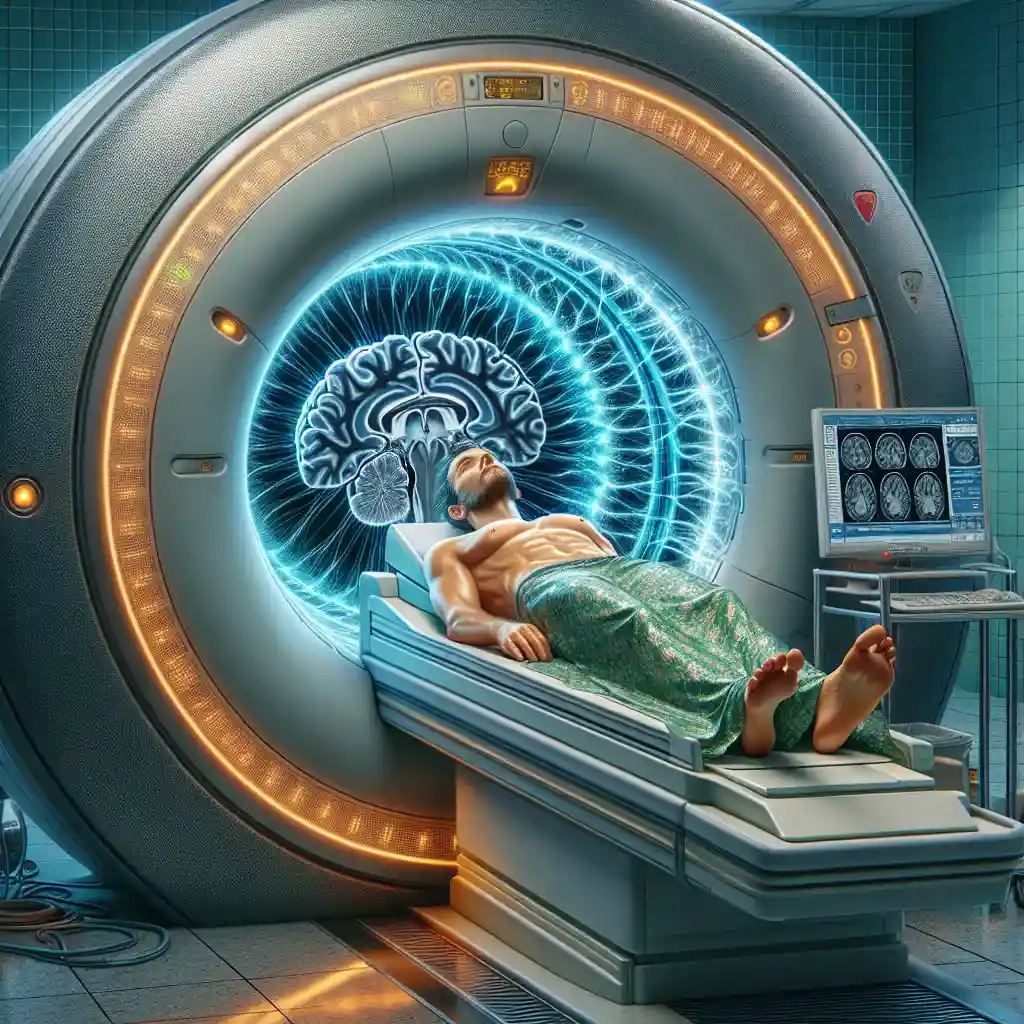

МРТ головного мозга

Магнитно-резонансная томография (МРТ) головного мозга – уникальный метод диагностики, который позволяет видеть мельчайшие изменения в структуре и состоянии мозга. Эта инновационная техника широко используется в неврологии, нейрохирургии и других медицинских областях для своевременного выявления различных патологий. Если вы хотите понять, как проходит процедура и что она показывает, то эта статья для вас!

МРТ головного мозга – безопасный и неинвазивный способ получить подробные снимки мозга в трёх измерениях с высоким разрешением. Большинство современных клиник Украины оснащены новейшим оборудованием, что гарантирует точность и надёжность результатов обследования.